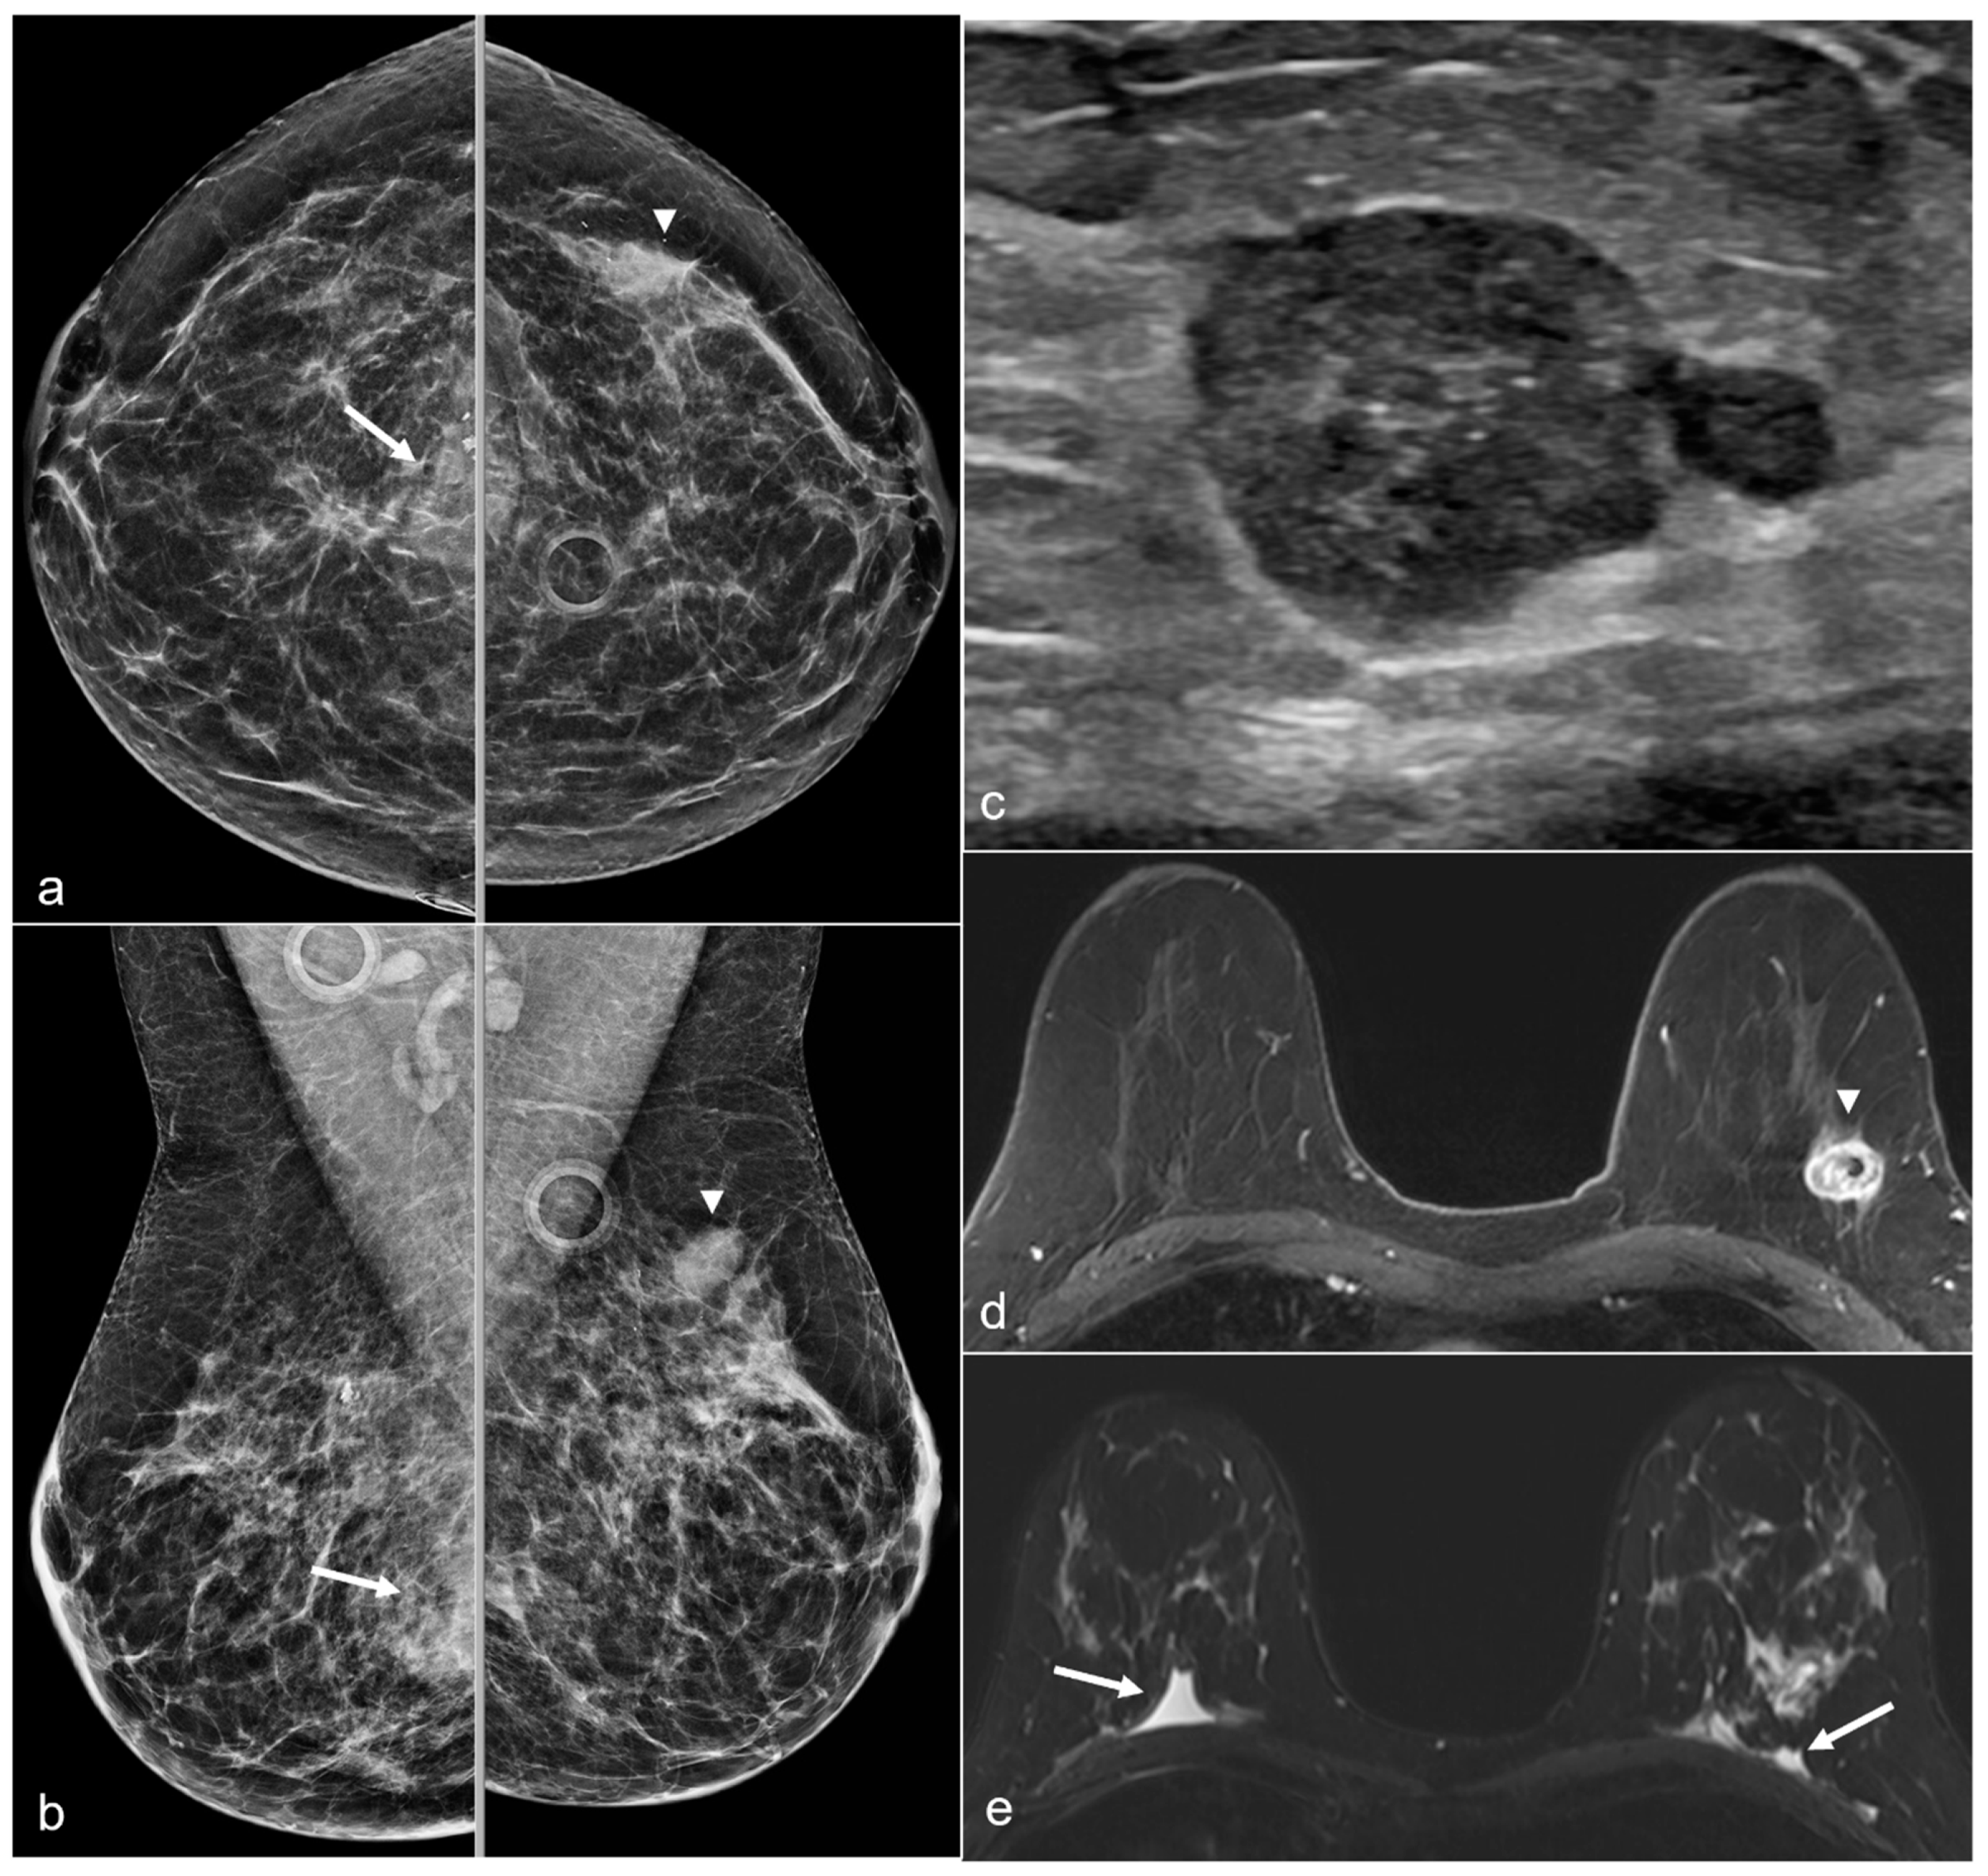

Figure 17. A 50-year-old woman with a history of subglandular silicone implants, status post BES. Screening mammograms with bilateral CC (a) and MLO views (b) demonstrate a mass in the left breast upper outer quadrant (arrowhead). BES changes are more prominent in the right breast with focal asymmetries in the prepectoral region (arrows) with dystrophic calcifications. Subsequent ultrasound examination of the left breast in the transverse plane (c) with ultrasound-guided biopsy revealed triple-negative invasive ductal carcinoma. T1-weighted post-contrast MRI (d) revealed a left breast enhancing mass (arrowhead) with a biopsy clip. There was also right greater than left prepectoral fluid (arrows) on the axial T2-weighted images (e).